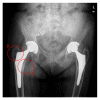

More than twenty years ago, hydroxyapatite (HA), calcium phosphate ceramics, was introduced as a coating for cementless hip prostheses. The choice of this ceramic is due to its composition being similar to organic apatite bone crystals. This ceramic is biocompatible, bioactive, and osteoconductive. These qualities facilitate the primary stability and osseointegration of implants. Our surgical experience includes the implantation of more than 4,000 cementless hydroxyapatite coated hip prostheses since 1990. The models implanted are coated with HA in the acetabulum and in the metaphyseal area of the stem. The results corresponding to survival and stability of implants were very satisfactory in the long-term. From our experience, HA-coated hip implants are a reliable alternative which can achieve long term survival, provided that certain requirements are met: good design selection, sound choice of bearing surfaces based on patient life expectancy, meticulous surgical technique, and indications based on adequate bone quality.